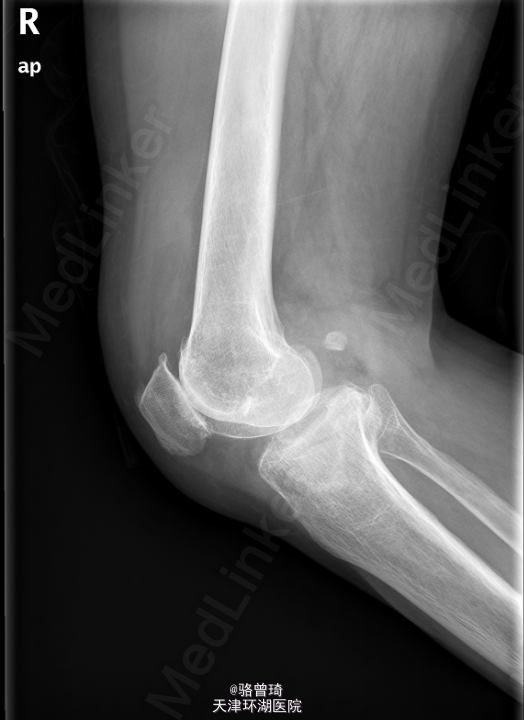

患者,女,68岁,因“摔伤致全身多处疼痛3小时”入院。

右膝关节肿胀,伴压痛,余肢体活动自如,双侧巴氏征阴性。右膝正侧位片示:右胫骨外侧平台塌陷骨折,右膝关节囊积液。右膝关节退行性骨关节病。右胫腓骨X片示:右胫骨外侧平台骨折,右胫骨中下段及右腓骨未见明显x线异常。